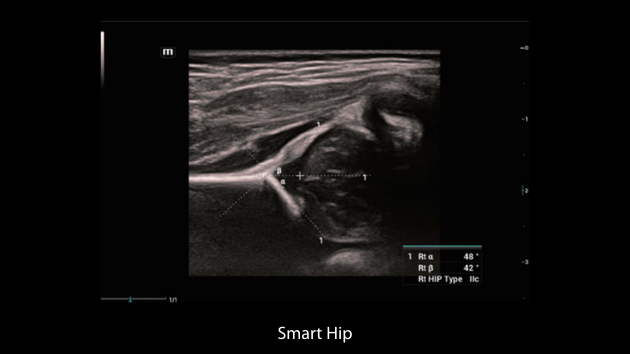

The Nuewa I9, dedicatedly designed for women and neonatal healthcare, providing an innovative experience from inside out.?These innovations are developed based on in-depth insights into complex clinical scenarios, providing accurate and timely answers as well as outstanding efficiency and remarkable user experience.

Clinical Images